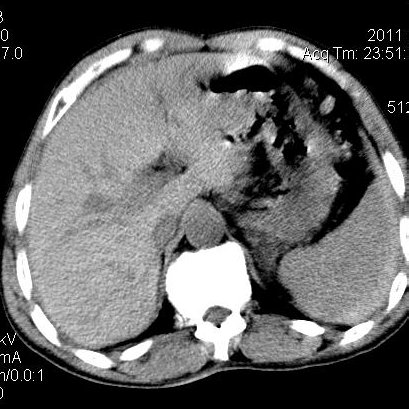

肝左叶发育异常

男性,55岁,骑摩托车摔倒后入院,自述右上腹疼痛

[backcolor=#FF0000]第一次诊断的时候也是这么肯定,可是床旁超声检查并没有发现明显异常,而且患者的一般症状都良好。还好临床只是保守治疗,没有立即手术,第二次复查的时候没有一点变化,又做了MRI检查,没有血肿,

这是一例肝左叶发育异常的,很个性吧~[/backcolor]